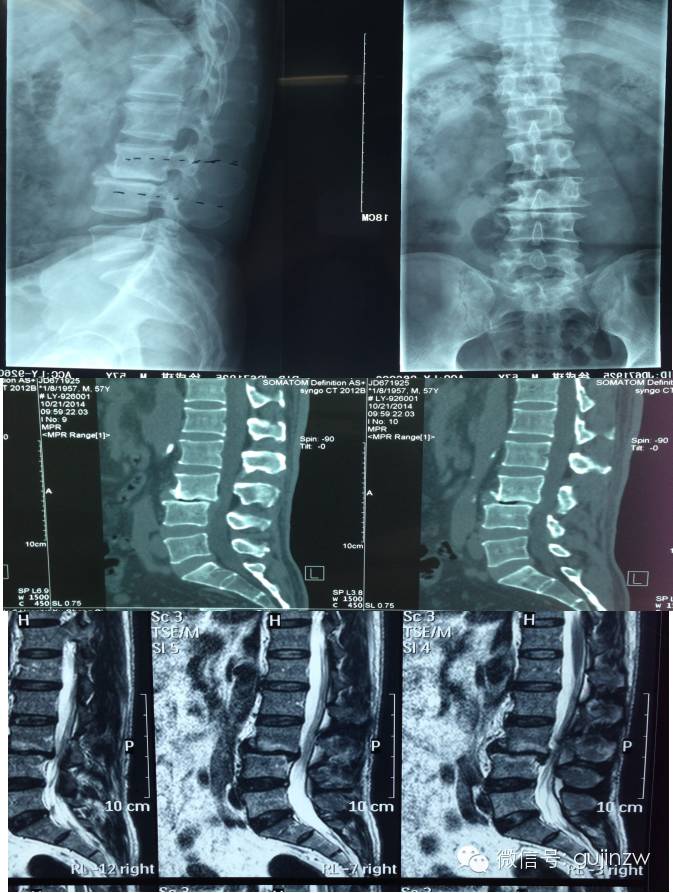

病例4:女,58岁,腰背疼痛5年,不能久坐久站和长时间行走

患者为58岁女性,有严重的“不可忍受”的下腰痛,不能长久行走和站立,腰痛ODI评分>50。保守治疗无效。